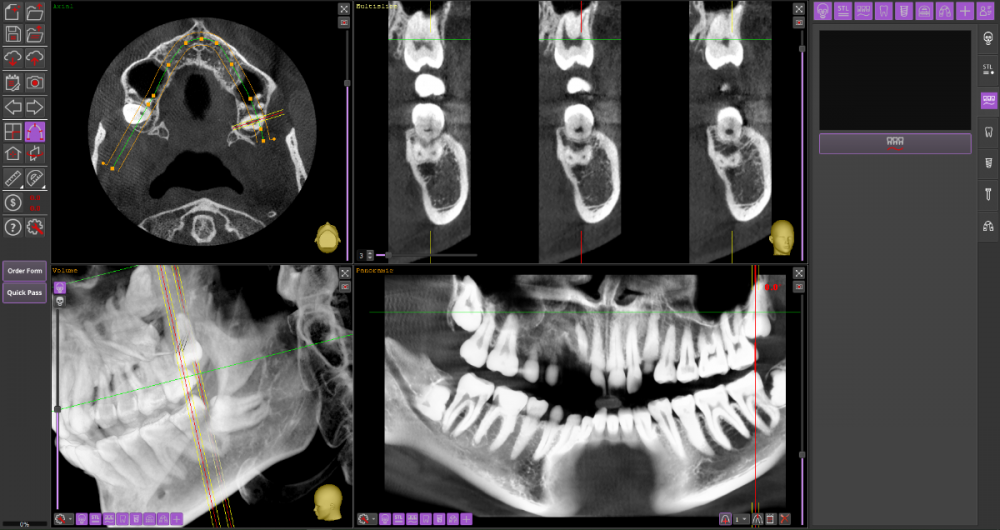

Прошу Вашего совета по поводу удаления восьмых зубов.

Из жалоб есть непродолжительная ноющая боль в правой нижней челюсти, не связанная с внешними раздражителями.

1. Необходимо ли удаление зубов мудрости?

2. Возможно ли удаление амбулаторно, без общего наркоза?

3. Нет ли риска для семёрок при удалении.

38_1.thumb.png.dcd277233a624fd58d77a364d41a7a23.png

38_2.thumb.png.29cf45d2d71efd9217558772656e2b38.png

Виновником боли в н.ч. справа может быть, например зуб 46, не только 48.

1. Удаление 8-х зубов скорее всего необходимо

2. Удаление амбулаторно вполне возможно. Общая анестезия (наркоз) совершенно необязательна, местной анестезии достаточно.

3. Несчастные случаи бывают, но крайне редко.